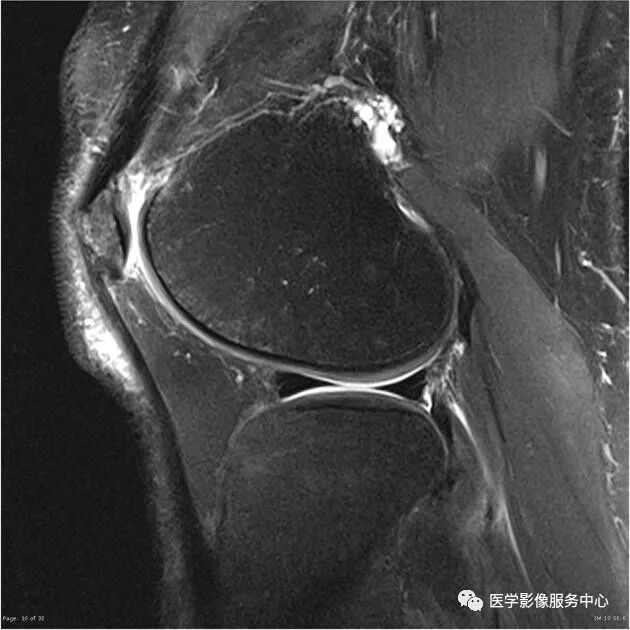

十三、关节囊附着

内侧半月板后角与后关节囊边缘之间的间隙可被误诊为半月板后角的垂直撕裂。